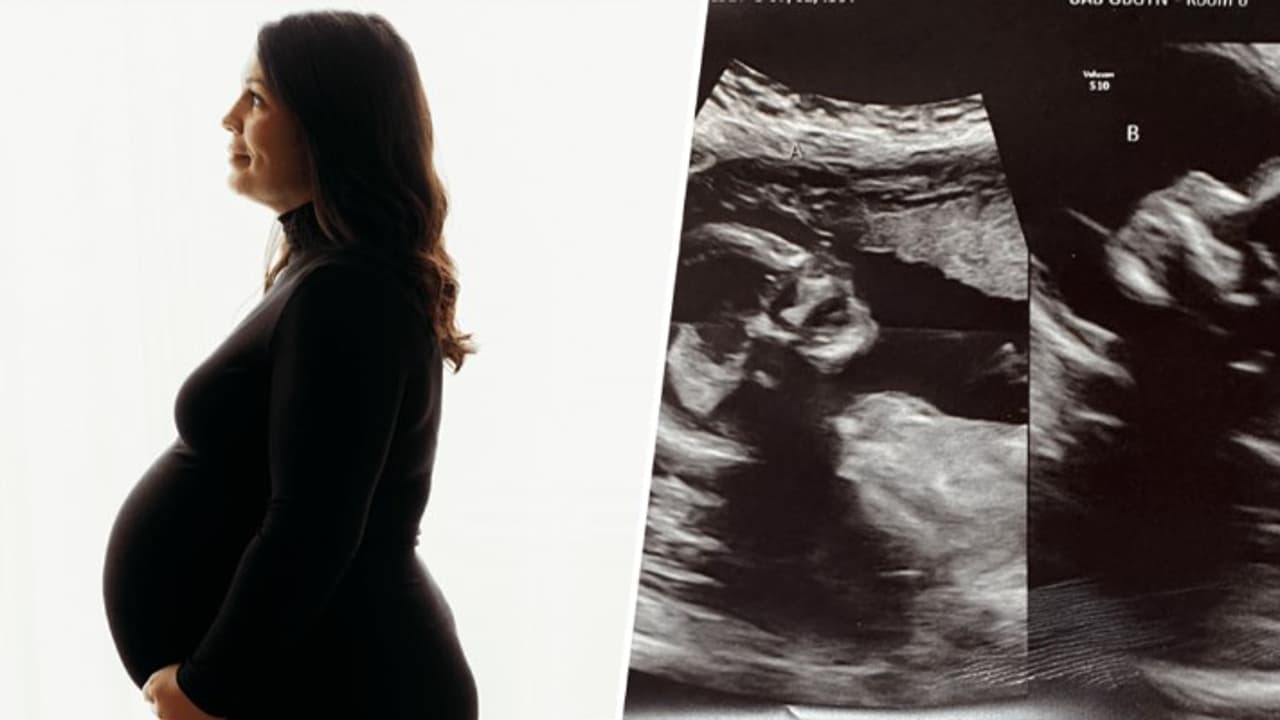

Woman With Two Uterus. इसे ईश्वर का चमत्कार ही कहेंगे कि किसी महिला को एक नहीं बल्कि दो गर्भाशय हैं। इतना ही नहीं यह भी क्लियर हो गया है कि महिला के दोनों गर्भाशय में भ्रूण पल रहे हैं और महिला दो बच्चों की उम्मीद कर रही है। जी हां, इस महिला का नाम केल्सी हैचर है, जो अल्बामा में रहती हैं। महिला जुड़वा बच्चों की उम्मीद कर रही है और यह जानकर पति-पत्नी ही नहीं बल्कि डॉक्टर भी हैरान हो गए हैं।

ऐसा बहुत ही रेयर होता है कि किसी महिला के दो गर्भाशय हों। महिला फिलहाल गर्भवती है और जब उनके पति ने इस रहस्य से पर्दा उठाया कि महिला के दोनों गर्भाशयों में भ्रूण का विकास हो रहा है तो पहली बार हैचर ने कहा कि- आप झूठ बोल रहे हैं। इसके बाद पति ने कहा कि वह झूठ नहीं बोल रहा है और यह पूरी तरह से सच है कि महिला के दोनों गर्भाशय में बच्चे पैदा होने की उम्मीद है। रिपोर्ट्स की मानें तो इस कपल को पहले से ही तीन बच्चे हैं। जिनकी उम्र 7 वर्ष, 4 वर्ष और 2 वर्ष है। माता-पिता ने परिवार बढ़ाने के लिए एक और बच्चे की प्लानिंग तो हैरान करने वाले नतीजे सामने आए। महिला को सामान्य जांच के लिए अल्ट्रासाउंड कराया गया तो यह आश्चर्यजनक नतीजा सामने आया। महिला मीडिय को बताया कि जब उसे यह पता चला तो उसके मुंह से सिर्फ एक ही शब्द निकला- हे भगवान।

अल्ट्रासाउंड के दौरान जब कपल को पता चला कि दोनों गर्भाशय में दो शिशु पल रहे हैं तो पहले हंसी आ गई और फिर आश्चर्य हुआ। जैसे ही उसने अल्ट्रासाउंड का रिजल्ट आया तो महिला ने कहा कि हे भगवान, वहां एक और है। हे भगवान। तब डॉक्टर ने कहा कि हां वहां एक नहीं दो हैं। अलबामा यूनिवर्सिटी हॉस्पिटल की प्रसूति एवं स्त्री रोग विशेषज्ञ डॉ. रिचर्ड डेविस ने दोहरे गर्भाशय से आने वाले चैलेंज के बारे में जानकारी दी। डॉक्टर ने कहा कि सी-सेक्शन सामान्य से थोड़ा अधिक जोखिम भरा है क्योंकि आपको प्रत्येक गर्भाशय में एक चीरा लगाना पड़ता है। यानी दो चीरे लगाने से खून की कमी हो सकती है। हैचर के दोनों गर्भाशय प्रकृति की अनूठी देन हैं लेकिन यह जोखिम भरा भी हो सकता है। डॉक्टर्स ने कहा कि महिला की सामान्य से ज्यादा निगरानी की जरूरत है।